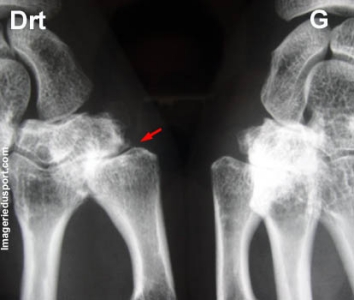

A - Radiographie de face, centrée sur les colonnes des 1ers rayons : Pincement trapézo-métacarpien, associé à des remaniements sous chondraux distaux du trapéze. Les anomalies sont prédominantes à droite ou l'on note une discréte subluxation de l'articulation. Pincement de l'interligne scapho-trapézien prédominant du coté gauche.

Arthrose trapézo métacarpienne ou rhizarthrose.